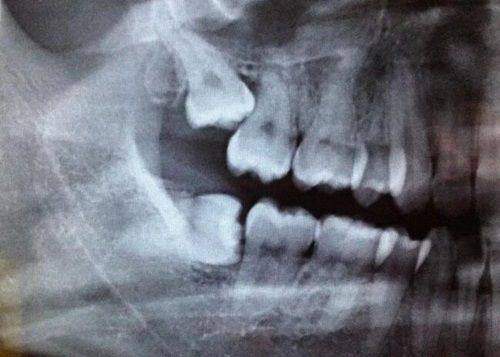

精良的设备是口腔诊所的重要支撑。北京微尔特五彩口腔诊所紧跟时代步伐,引进了一系列国内外精良的口腔诊疗设备。例如,数字化口腔全景机能够快速、正确地拍摄口腔全景图像,为医生提供详细的诊断依据;精良的种植牙设备可以实现精细种植,大大提高了种植牙的成功几率和稳定性。这些设备不仅提高了治疗的效率和正确性,还减少了患者的痛苦和治疗时间,让患者在舒适的环境中解决口腔问题。